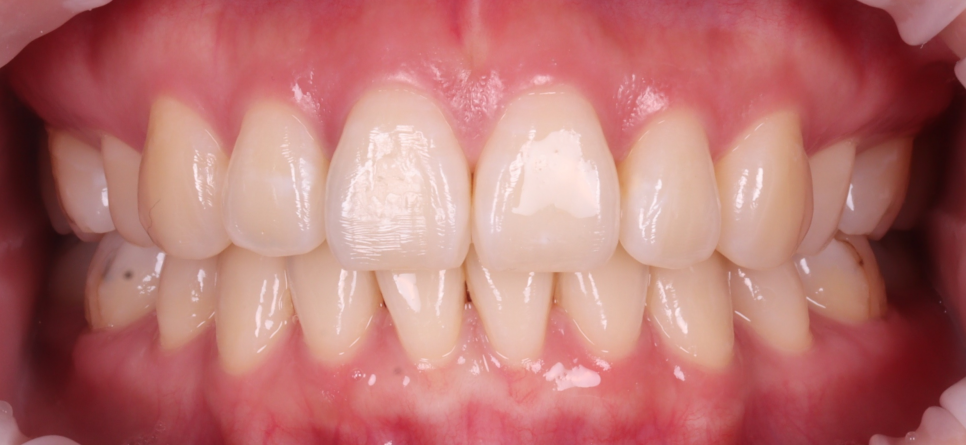

앞니 충치, 어떻게 신경치료 없이 레진으로 해결할 수 있었을까?

앞니 충치는 깊긴 했지만 바로 신경치료나 크라운이 필요할 정도는 아니었어요.

충치를 확인해 보니 깊긴 했지만, 신경치료까지 필요할 정도는 아니라고 판단했습니다.

그래서 조심스레 제거 후, 레진으로 마무리하기로 했어요.

앞니 레진은 ‘간단한 진료’라는 인식이 많지만 사실은 굉장히 섬세하고 정말 손이 많이 가는 작업이에요^^;

러버댐을 장착하고 수분이 닿지 않도록 격리한 다음, 한 층씩 빛으로 굳히면서 양옆 치아와 자연스럽게 어울리도록 형태를 잡아줘야 해요.